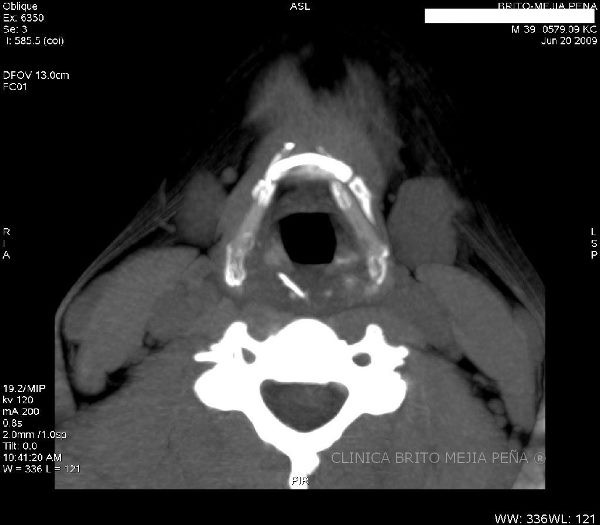

Espina en espacio retrofaríngeo

Post Image